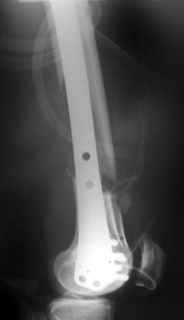

Re: Open supracondylar femur fx

This is what we have done... As generally true for LISS look at the bone not the hardware.

There are two more srews above. The one not completely in got damaged head.